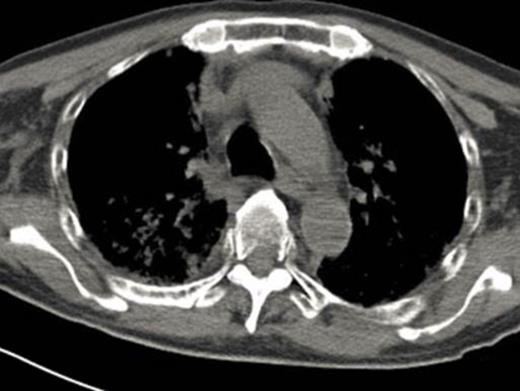

A 64-year-old male with chronic low back pain presented to the emergency department with new onset severe mid back pain radiating to bilateral shoulders. CT scan, performed to rule out aortic dissection, demonstrated multiple lytic lesions throughout the bony skeleton and a compression fracture at T7 vertebral body with epidural extension of soft tissue. A bone survey confirmed CT scan findings, and subsequent bone marrow biopsy confirmed the diagnosis of MM. He received radiation therapy to the thoracic spine and completed 2 cycles of CyBorD regimen (Cyclophosphamide 300 mg/m2 by mouth, BTZ 1.5 mg/m2 sub-cutaneous, and Dexamethasone 40 mg by mouth each on day 1, 8, 15 and 22). Three days after the completion of the second cycle, he was admitted to hospital with respiratory distress. CT chest (Image 2) showed new interval appearance of bilateral perihilar groundglass opacities, peribronchial and interstitial thickening predominantly in the upper lobes not seen in prior scan (Image 1). There were no other signs or symptoms of pneumonia such as leukocytosis, fever or cough. After some benefit from oral prednisone, he was discharged with a tapering dose of the same. Unfortunately, patient was readmitted with worsening respiratory distress 4 days later. A repeat CT scan of the chest showed resolution of previously well-defined areas of perihilar ground glass opacities but development of hazy areas of ground-glass opacification throughout both lungs with more confluent abnormalities in bilateral lower lobes (Image 3). Patient was treated with high dose methyl-prednisone and noninvasive positive pressure ventilation without any improvement. Family requested do-not-resuscitate and do-not-intubate status. Patient died on 10th day of the admission.